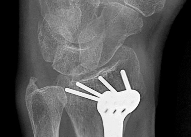

Question 2:

A 12-year-old boy presents with left thigh pain, an antalgic gait, and an externally rotated left lower extremity. Radiographs demonstrate the pathology shown. Which of the following is considered an absolute indication for prophylactic pinning of the asymptomatic, contralateral hip in a patient presenting with Slipped Capital Femoral Epiphysis (SCFE)?

Correct Answer: Underlying endocrine disorder (e.g., hypothyroidism)

Explanation:

SCFE is characterized by a displacement of the proximal femoral epiphysis. Prophylactic pinning of the contralateral hip is somewhat controversial but generally recommended in patients with a high risk of subsequent contralateral slip. Absolute indications or highly strong recommendations for prophylactic contralateral pinning include an underlying endocrine disorder (such as hypothyroidism or growth hormone deficiency), renal osteodystrophy, previous radiation therapy, and presentation at a very young age (e.g., < 10 years). Endocrine disorders dramatically increase the risk of bilateral involvement, often occurring simultaneously or sequentially.